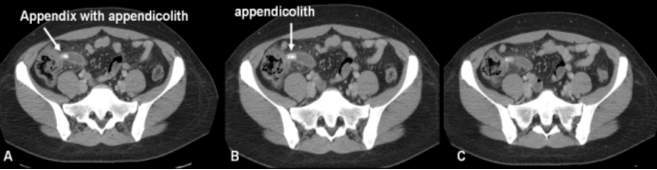

Making the diagnosis of appendicitis